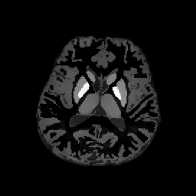

Table 1 summarizes the relative error and the SSIM of the direct approaches (Eqs. 1.5 and 1.6) and the wavelet frame regularization approaches, and Figs. 8 and 9 present visual comparisons of the results. In addition, Table 2 summarizes the aforementioned indices of the direct approaches and the TGV regularization approaches, and Figs. 10 and 11 depict the visual comparisons. We can see that both the Frame-HIRE and the TGV-HIRE consistently outperform the existing direct approaches, the integral approaches, and the differential approaches in both cases. At first glance, this verifies the convention that the regularization based models in general performs better in solving the ill-posed inverse problem of QSM than the direct methods [27, 51]. Most importantly, this result demonstrates that the measured local field data obtained from the phase of a complex GRE MR signal contains the harmonic incompatibility other than the noise, which agrees with our theoretical discovery, and the performance gain mainly comes from taking both the noise in the measured data and the harmonic incompatibility (the incompatibility other than the noise) at the same time. Meanwhile, since this harmonic incompatibility is not taken into account in the integral approaches, the reconstructed susceptibility images contain the shadow artifacts as shown in Figs. 8d, 9d, 10d and 11d. The differential approaches can remove the harmonic incompatibility in the measured data in advance, leading to the shadow artifact removal compared to the integral approach. However, since the noise in blsubscript𝑏𝑙b_{l} was amplified by {\mathscr{L}}, the final reconstructed images contain the streaking artifacts as shown in Figs. 8e, 9e, 10e and 11e, leading to the degradation in indices at the same time.

Figure 8: Sagittal slice images comparing QSM reconstruction methods for the brain phantom experiments. All sagittal slice images of brain phantom experimental results are displayed in the window level [0.03,0.07]0.030.07[-0.03,0.07] for the fair comparison.

Figure 9: Axial slice images comparing QSM reconstruction methods for the brain phantom experiments with the wavelet frame regularization. All axial slice images of brain phantom experimental results are displayed in the window level [0.03,0.19]0.030.19[-0.03,0.19] for the fair comparison.